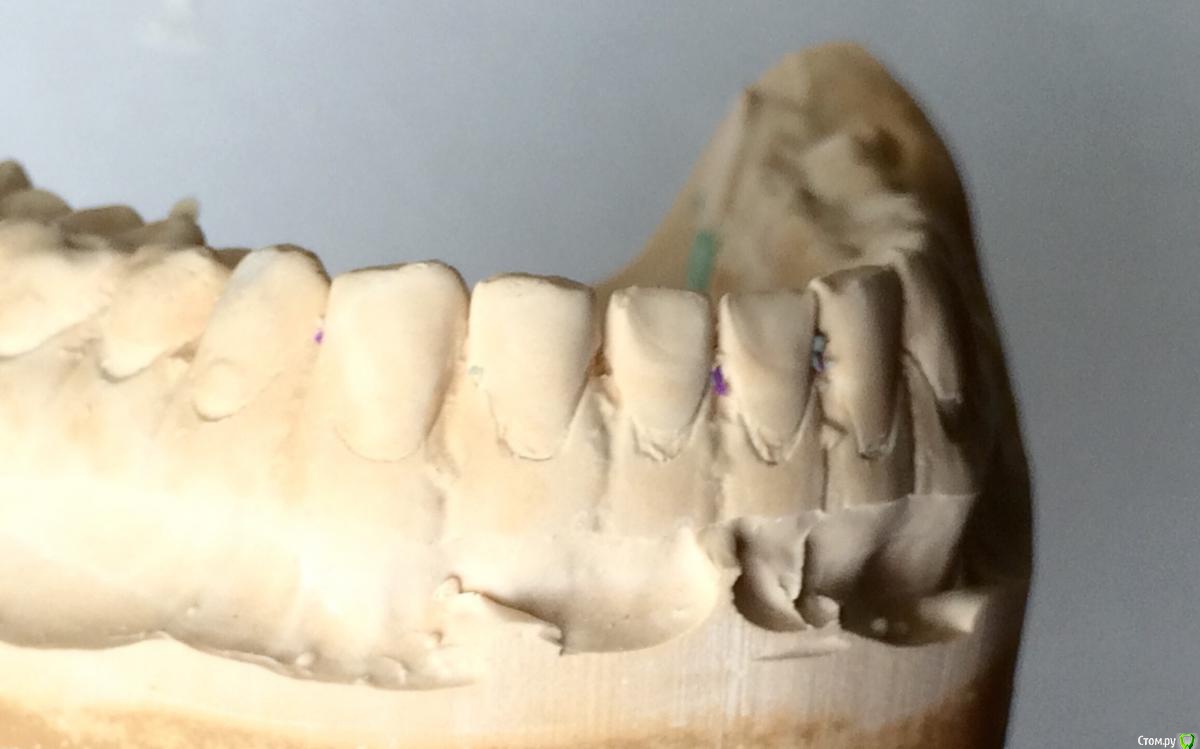

Larnary Опубликовано 28 июля, 2015 Поделиться Опубликовано 28 июля, 2015 (изменено) Добрый день!Ко мне обратилась пациент 1988 гр с жалобой на стираемость зубов и постоянные сколы пломб.Объективно небная поверхность верхних резцов стерта до дентина. Окклюзионная стираемость жевательной группы зубов.Прошу помочь с выявлением причины такой стираемости зубов и оптимальноно метода лечения Изменено 28 июля, 2015 пользователем Larnary Ссылка на комментарий

Larnary Опубликовано 28 июля, 2015 Автор Поделиться Опубликовано 28 июля, 2015 (изменено) Видно окклюзионнык интерференции в области 37 и 47.На днях удален 38 и дальше будут удалены остальные восьмерки. На ТРГ мне видится небольшая ретрузия верхних резцов,дистальный прикус. Так же левпя окклюзионная кривая более выраженная,чем правая Изменено 28 июля, 2015 пользователем Larnary 1 Ссылка на комментарий

Bobby Опубликовано 29 июля, 2015 Поделиться Опубликовано 29 июля, 2015 Фасетки стираемости на нёбных поверхностях верхних резцов и вестибулярных поверхностях нижних резцов обусловлены малым оверджетом - недостаточная щель по саггитали, поэтому и будут колоться реставрации, а ткани зубов истираться. Фрадеани про это на своём курсе рассказывал и показывал видео как это диагносцировать и что с этим делать. Что вообще хочет пациентка и на что готова? Эти вопросы лучше сразу решать на первичной консультации, а то делаете диагностики, всё рассчитываете, распинаетесь, а они потом: "ой, я пока не готов/а к такому плану лечения" и всё заканчивается композитной мазнёй в другой клинике. 5 Ссылка на комментарий